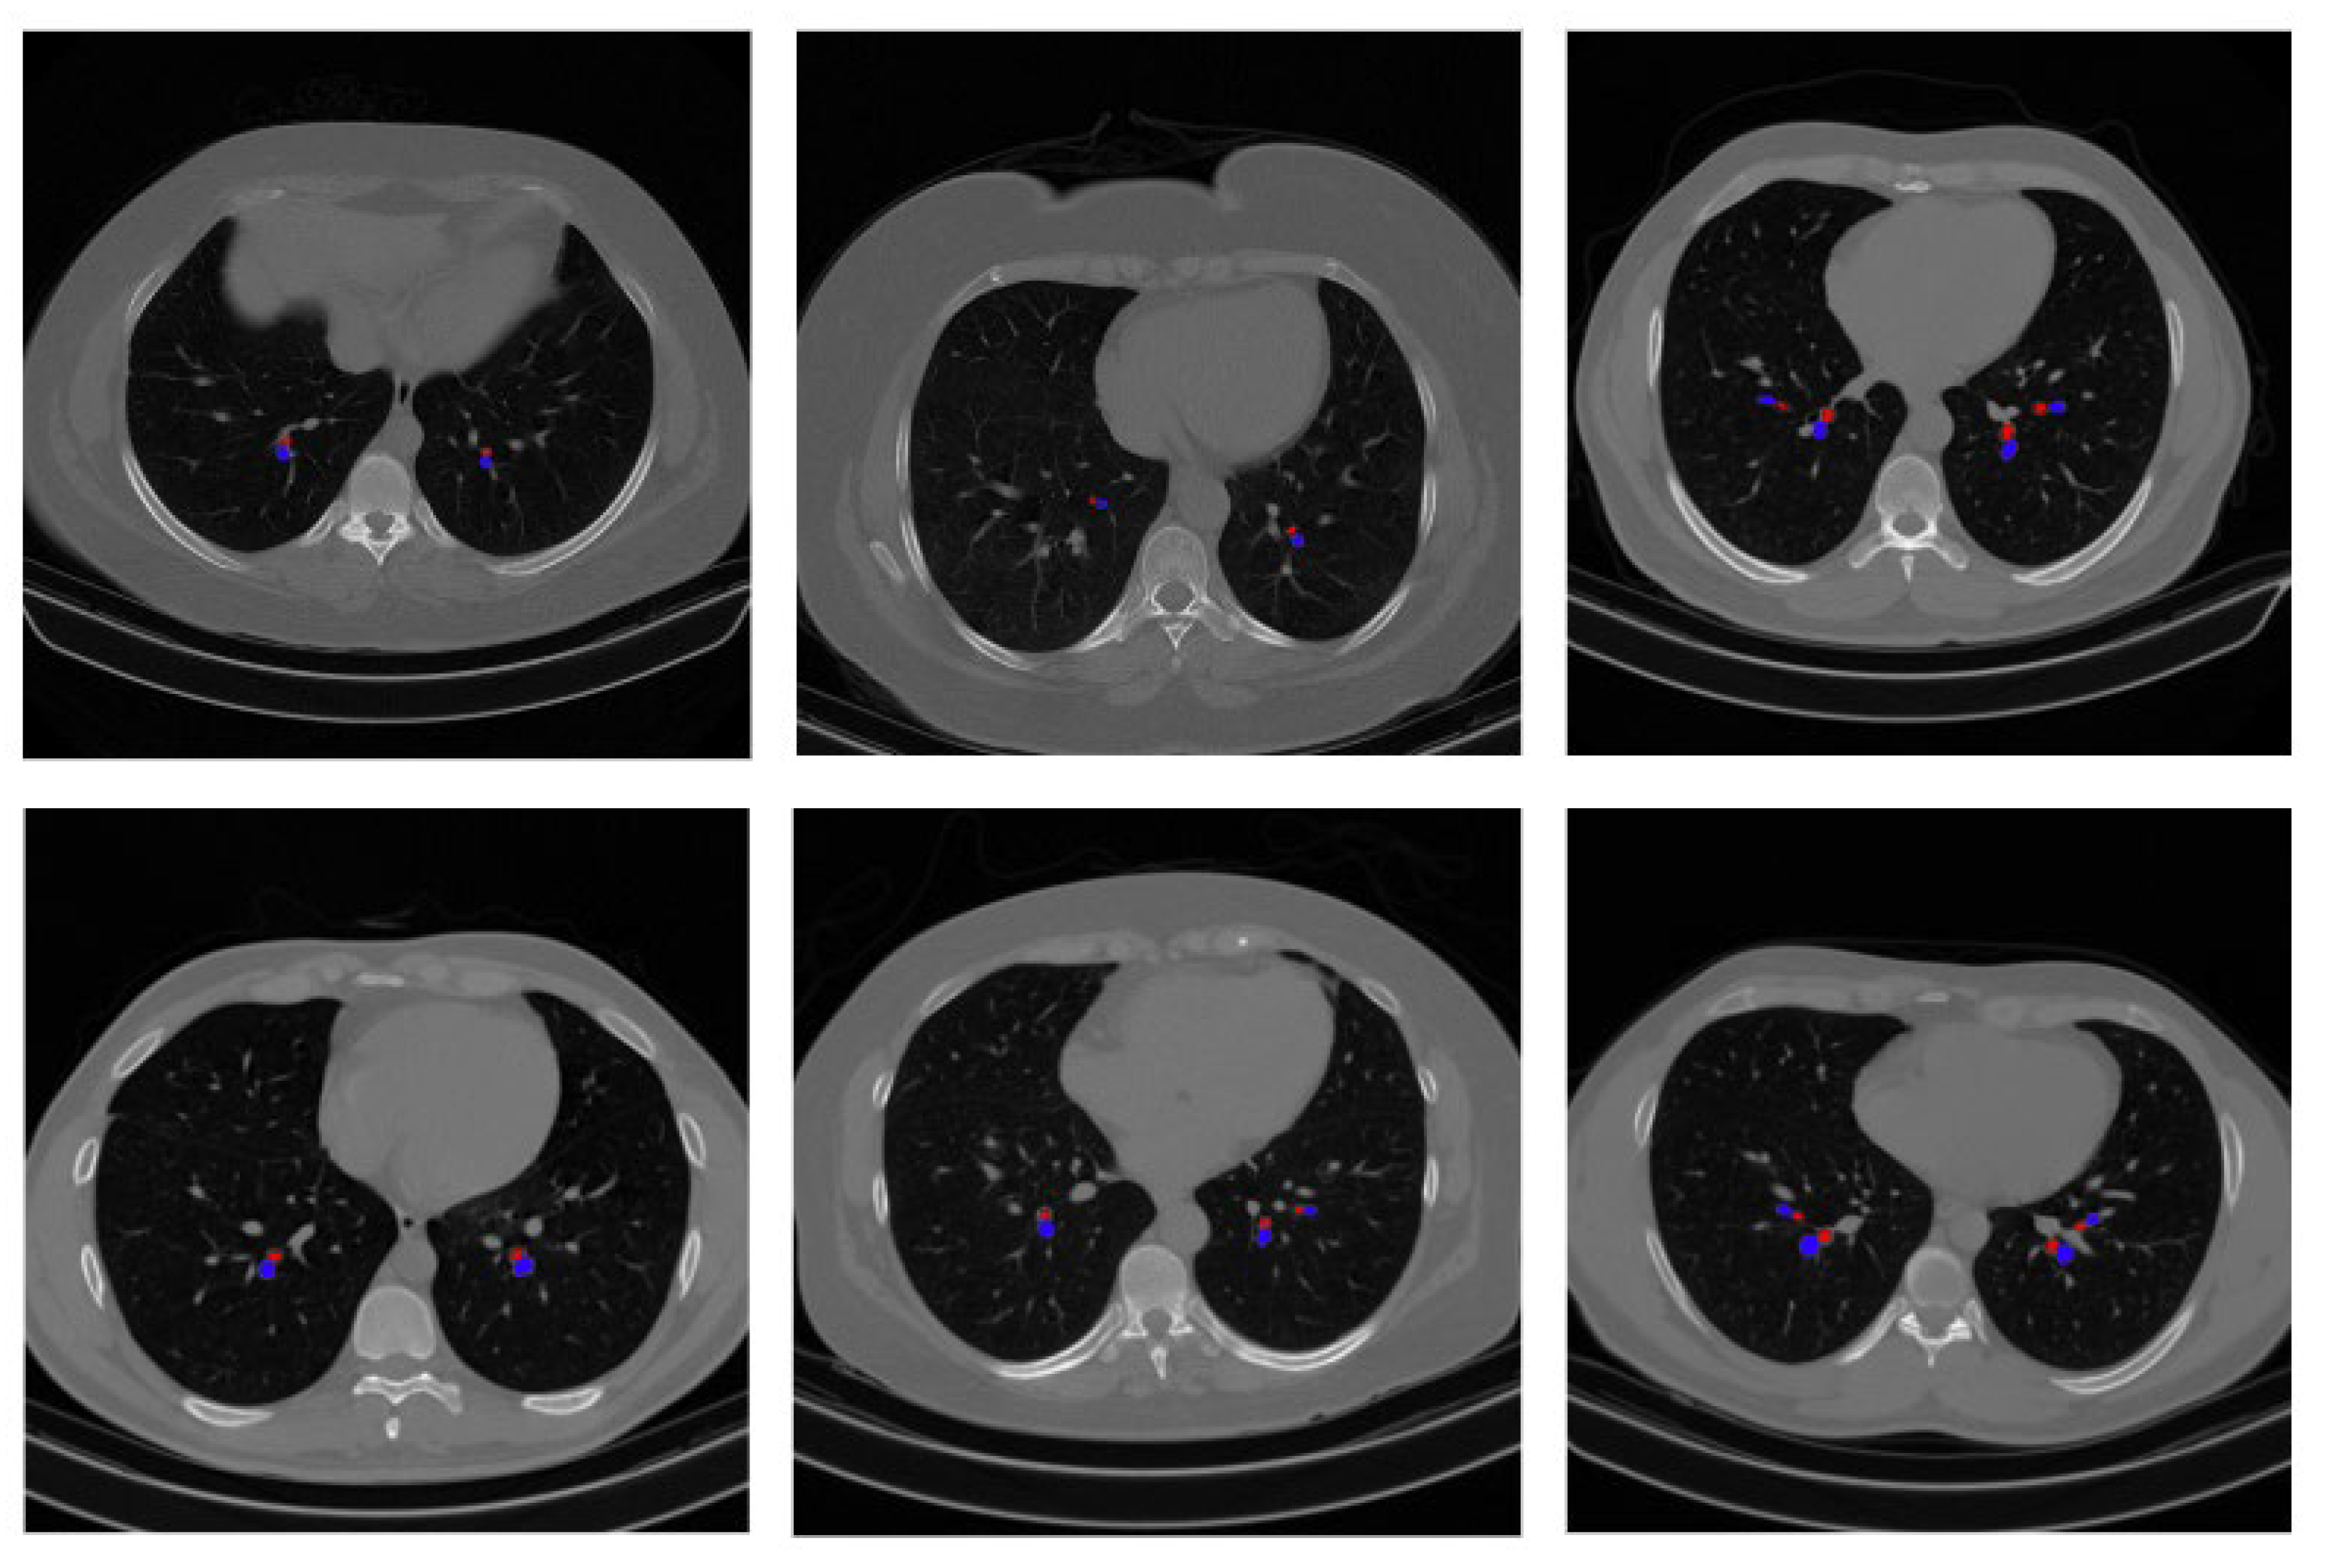

In this experiment, our proposed approach of detecting BA pairs is applied to the same lung disease CT scan dataset. The output of detected BA pairs on the public dataset is illustrated in Figure 18. Moreover, a total of 100 random scans from the public dataset are validated by the radiologist to confirm that the detected BA pairs are genuine, which further evaluates the effectiveness of the proposed approach.

Figure 18.

Example output of BA pair detection process on a public dataset.